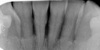

Cas 1 : Parodontite agressive nécessitant une attelle avant surfaçage

En cas d'atteinte parodontale avancée où l'os alvéolaire a beaucoup "fondu" et où les dents ne sont plus "tenues" que par le tartre, il est nécessaire de réaliser et coller l'attelle AVANT de réaliser le surfaçage

Dans les cas extrêmes, une attelle provisoire de type « orthodontique » peut être proposée avant le traitement parodontal.